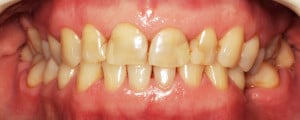

Wykonano higienizację jamy ustnej poprzez usunięcie kamienia nazębnego skalerem ultradżwiękowym, zdjęciem osadu i płytki nazębnej poprzez piaskowanie air flow plus oraz classic, a następnie wypolerowaniu gumką ze specjalistyczną pastą polerską:

Po wypłukaniu jamy ustnej przez pacjentkę rozcieńczonym eludril classic przystąpiono do fluoryzacji preparatem clinpro varnish. Odizolowano wałeczkami ligniny zęby od śliny aby zapewnić ich suchość, a następnie pędzelkiem nałożono preparat na wszystkie zęby:

Celem fluoryzacji jest zmniejszenie nadwrażliwości zębów oraz wzmocnienie ich przez odbudowę mikroubytków szkliwa.